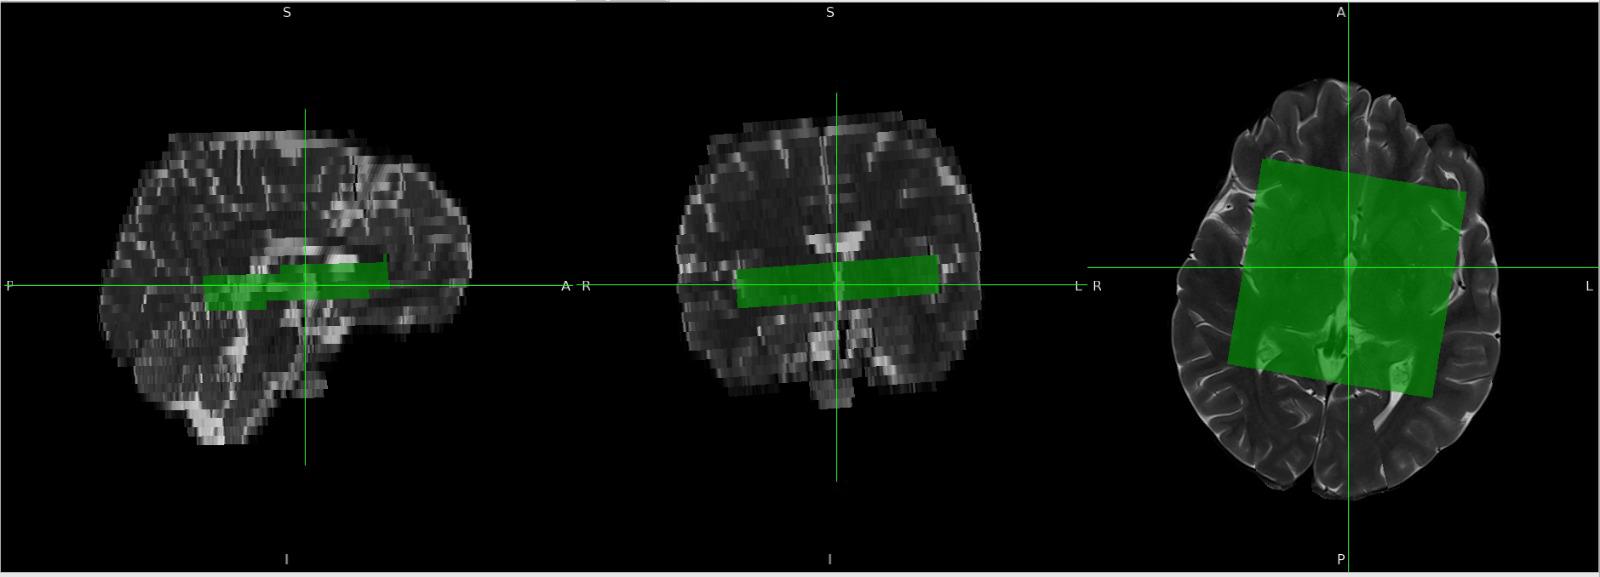

Last week, I tried several approaches to derive orientation values, and I think I have found a method to overcome this issue. Instead of using the SlabOrientation values, I derived rotation angles (in radians) from the RowVector and ColumnVector matrices by decomposing them into Euler angles. I tested this approach on multiple datasets, and so far it appears to work well.

For voxel positioning, I used the MidSlabPosition matrix instead of PositionVector. Apart from these changes, I did not make any major modifications to the existing code.